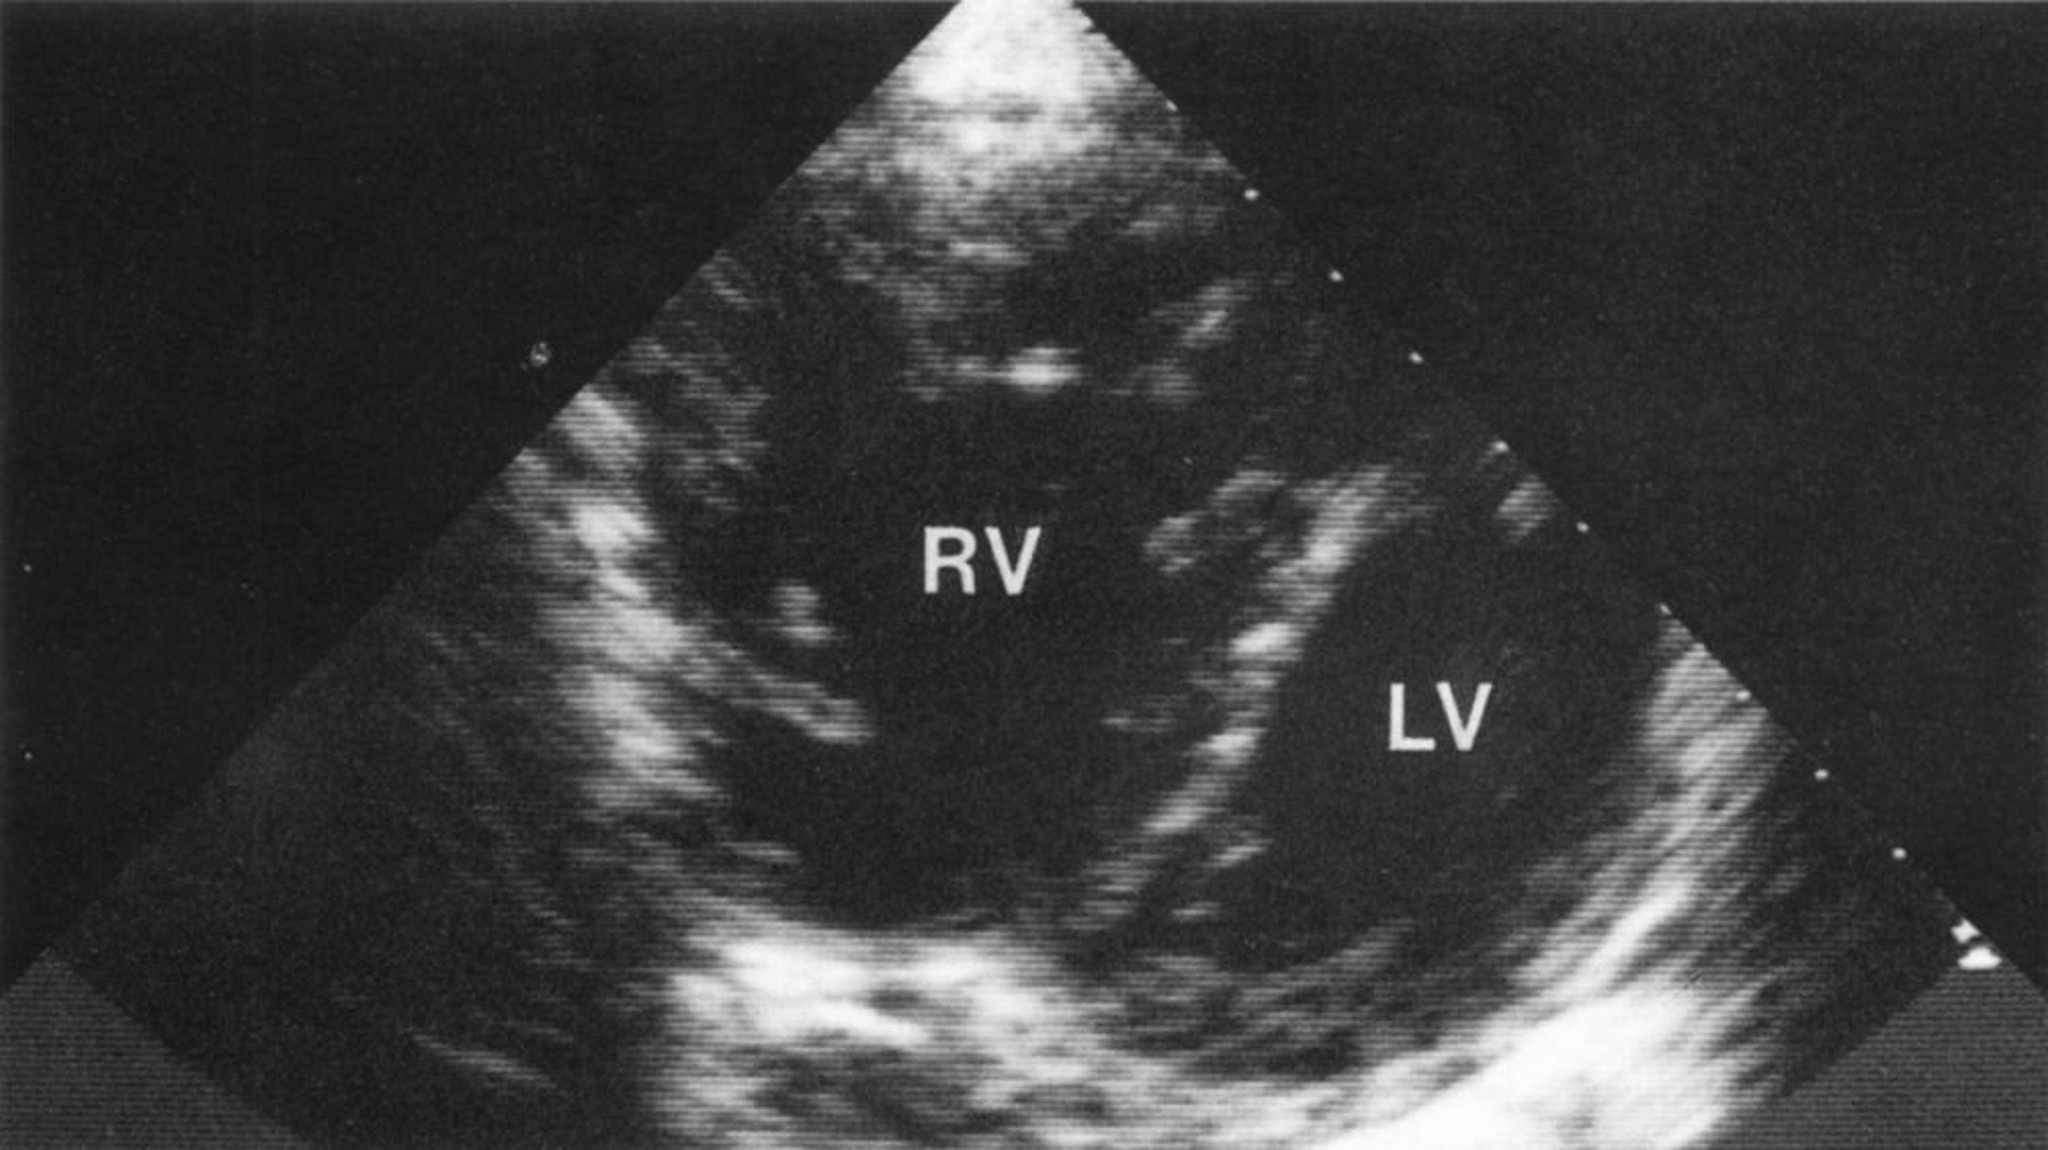

Right heart failure is a clinical diagnosis, composed of supportive symptoms and physical examination findings. Cardiac imaging, particularly echocardiography and cardiac MRI, is used to confirm right ventricular dysfunction, including dilatation and impaired systolic function. Both imaging modalities can identify previously undiagnosed structural, functional, and congenital abnormalities. Right atrial enlargement and functional tricuspid valve regurgitation are also supportive findings.

Echocardiography can assess RV systolic pressure but is often technically limited by the lung disorder; Cardiac MRI can quantitatively assess RV size and function. Right heart catheterization may be required for confirmation. Electrocardiography can identify arrhythmia as well as subtle findings of right ventricle hypertrophy and dilation and right atrial or ventricular dilation. Measurement of brain (B-type) natriuretic peptide (BNP) or N-terminal-pro-BNP (NT-pro-BNP) levels can support the diagnosis of heart failure as well as track clinical response over time.